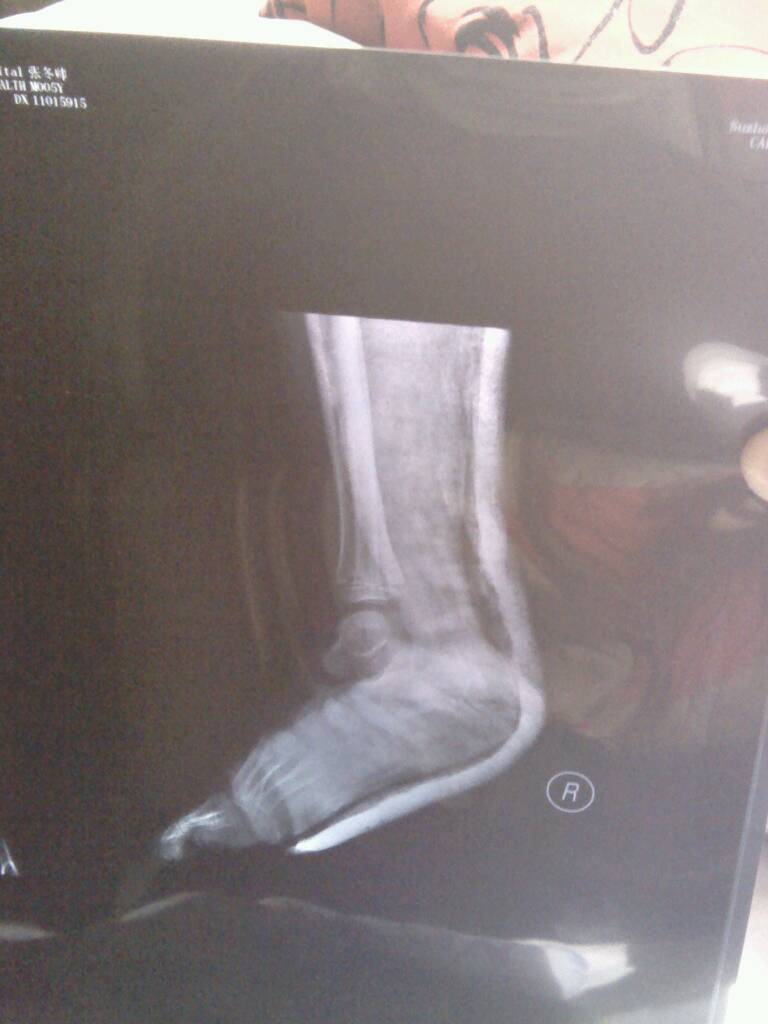

你好我家小孩五岁脚后骨骨折已有十几天,现在消肿也不疼了,老在床上动来动去,会不会错位啊,请专家帮忙看x片,骨折严重吗?一个星期复查拍的,因怕辐射对小孩不好,不敢频繁拍,

病情分析: 你好,看了你家宝宝的片子,知道脚踝部骨折,用石膏进行外固定。 指导意见: 虽然感觉不会发生错位,但是建议你还是应该去医院定期复查,一旦出现问题及时处理。